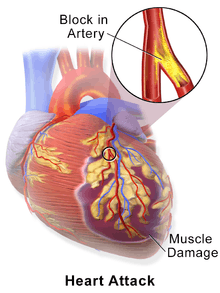

Myocardial infarction (MI) or acute myocardial infarction (AMI), commonly known as a heart attack, occurs when blood flow stops to a part of the heart causing damage to the heart muscle. The most common symptom is chest pain or discomfort which may travel into the shoulder, arm, back, neck, or jaw. Often it is in the center or left side of the chest and lasts for more than a few minutes. The discomfort may occasionally feel like heartburn. Other symptoms may include shortness of breath, nausea, feeling faint, a cold sweat, or feeling tired.[1] About 30% of people have atypical symptoms,[2] with women more likely than men to present atypically.[3] Among those over 75 years old, about 5% have had an MI with little or no history of symptoms.[4] An MI may cause heart failure, an irregular heartbeat, or cardiac arrest.[5][6]

Most MIs occur due to coronary artery disease.[5] Risk factors include high blood pressure, smoking, diabetes, lack of exercise, obesity, high blood cholesterol, poor diet, and excessive alcohol intake, among others.[7][8] The mechanism of an MI often involves the complete blockage of a coronary artery caused by a rupture of an atherosclerotic plaque.[5] MIs are less commonly caused by coronary artery spasms, which may be due to cocaine, significant emotional stress, and extreme cold, among others.[9][10] A number of tests are useful to help with diagnosis, including electrocardiograms (ECGs), blood tests, and coronary angiography.[11] An ECG may confirm an ST elevation MI if ST elevation is present.[2] Commonly used blood tests include troponin and less often creatine kinase MB.[11]

Acute myocardial infarction refers to two subtypes of acute coronary syndrome, namely non-ST-elevated and ST-elevated MIs, which are most frequently (but not always) a manifestation of coronary artery disease.[54] The most common triggering event is the disruption of an atherosclerotic plaque in an epicardial coronary artery, which leads to a clotting cascade, sometimes resulting in total occlusion of the artery.[55][56] Atherosclerosis is the gradual buildup of cholesterol and fibrous tissue in plaques in the wall of arteries (in this case, the coronary arteries), typically over decades.[57] Bloodstream column irregularities visible on angiography reflect artery lumen narrowing as a result of decades of advancing atherosclerosis.[58] Plaques can become unstable, rupture, and additionally promote the formation of a blood clot that occludes the artery; this can occur in minutes. When a severe enough plaque rupture occurs in the coronary arteries, it leads to MI (necrosis of downstream myocardium).[55][56] It is estimated that one billion cardiac cells are lost in a typical MI.[59]